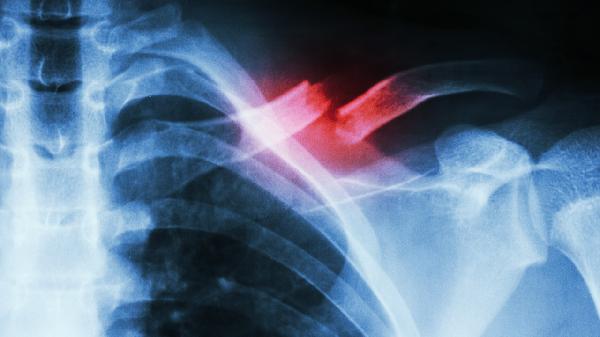

锁骨骨折通常由外伤、运动损伤、骨质疏松、肿瘤转移或先天性骨病等原因引起。锁骨骨折可能与直接暴力撞击、跌倒时手臂外展撑地、骨密度降低、恶性肿瘤侵蚀或成骨不全症等因素有关,常表现为局部肿胀、活动受限、畸形隆起等症状。

锁骨位置表浅,遭受直接暴力撞击如车祸、重物砸伤时易发生骨折。高处坠落或滑倒时手臂外展撑地,外力经肩关节传导至锁骨中段也可导致骨折。此类骨折多为横行或粉碎性,需通过X线检查确诊,急性期需用锁骨带固定4-6周,严重移位时需手术复位内固定。